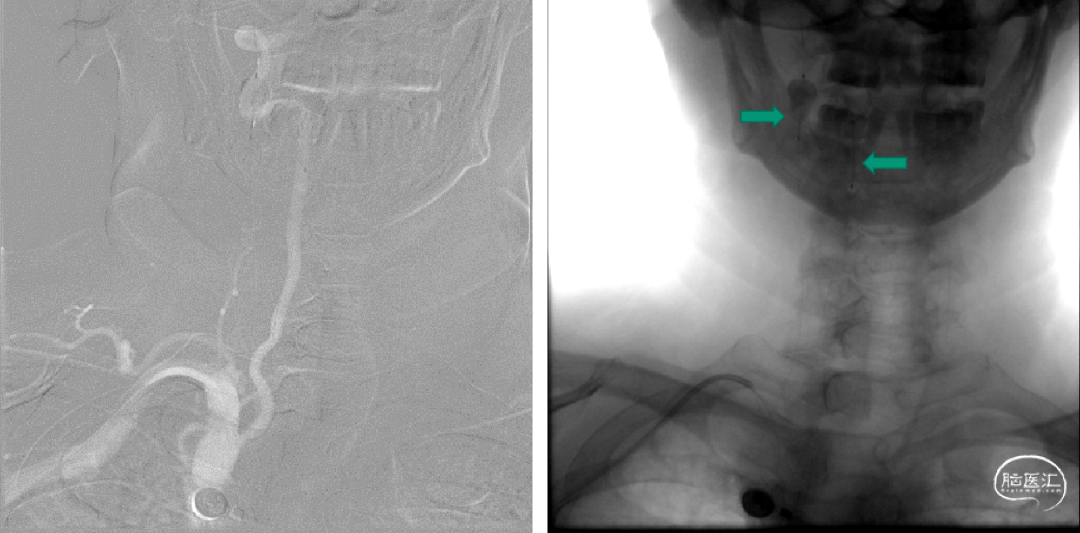

继续筛查颅外段血管完善颈部血管CTA:可见头臂干钙化斑块,伴低密度影,考虑附壁血栓。

考虑动脉硬化斑块继发血栓。

复查颈部血管CTA提示血栓较前明显减小。

抗凝一周后复查颈部血管CTA,血栓明显减小,血栓附着于头臂干左前侧壁。

此时患者的头臂干血栓应属于漂浮血栓(free floating thrombus, FFT), 即一端附着于动脉壁,一端游离于血管腔内,此类型血栓会随收缩压、舒张压交替至血栓来回摆动,脱落风险较高。

附壁血栓可见链接蒂结构,附壁血栓逐渐溶解,链接蒂结构也可见消解,如继续溶解可能出现链接蒂断裂,导致远端血栓脱落至远端栓塞。

DSA:经股动脉行主动脉弓造影显示:二型弓,头臂干可见充盈缺损,头臂干分叉处迂曲。

125cm MPA配合泥鳅导丝选入右侧锁骨下动脉内,同轴技术跟进NeuronMAX至头臂干起始处造影可见血栓影。